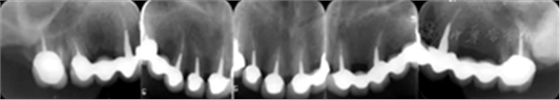

3.影像學(xué)檢查:

全口根尖X線片示鄰面骨嵴頂影像模糊;根管欠填、根充不致密,、未見根管治療影像,、根尖周可見低密度影像(圖2)。

圖2 患者初診時全口根尖X線片